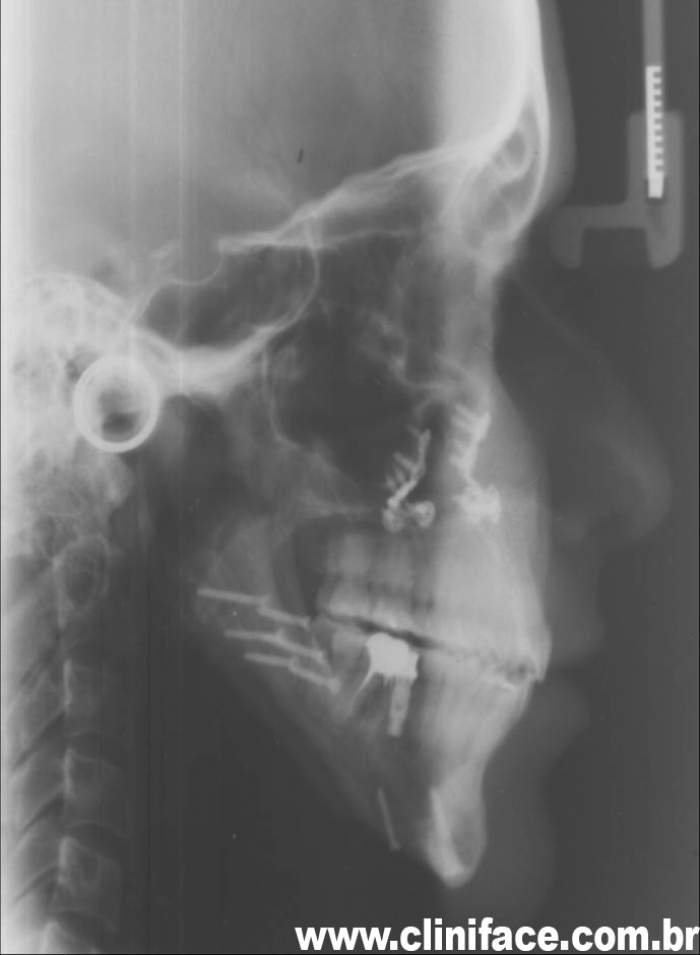

Telerradiografia inicial